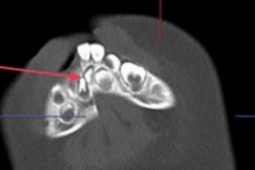

Đây là một ca bệnh đặc biệt phức tạp, do xương gò má bị can sai, đâm sâu và dính chặt vào xương thái dương, các mảnh xương vỡ theo 3 chiều không gian.

Ca phẫu thuật được tiến hành bằng đường mổ coronal, kết hợp lập kế hoạch điều trị ảo trên phần mềm chuyên dụng, thiết kế và sản xuất bộ công cụ hướng dẫn phẫu thuật cá nhân hóa, cùng với hệ thống định vị phẫu thuật (navigation) để xác định chính xác các vị trí khó và nguy hiểm như ổ mắt, nền sọ, giúp tăng độ chính xác và giảm thiểu rủi ro.